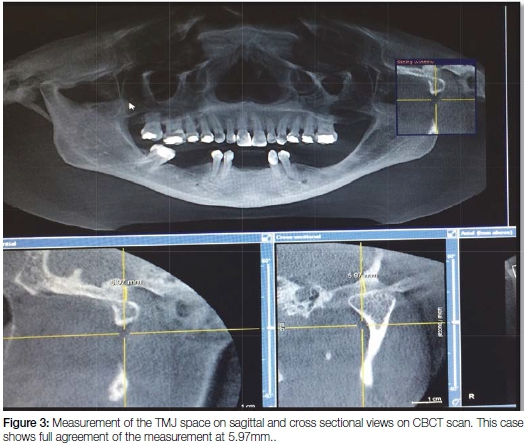

The number of radiographs taken at the Radiology section of the Wits School of Oral Health Sciences includes approximately 50 Pans per day and about 10 CBCT scans per week. This routine provided sufficient material for the current project. From the archives of the Radiology Section, the records of sixty three patients who had been subjected to both a Pan and a CBCT scan between March and July 2015 inclusive were randomly selected, using the Excel random number selection programme, and were assessed for inclusion in the study. All radiographic views were required to be of highly acceptable quality. Seventeen cases were excluded from the study for reasons of the patient having undergone condylar fusion, condylectomy, condylar prosthesis or another form of condylar pathosis. Hence a total of 92 radiographs of joint spaces were included. Each radiograph demonstrated completely discernible TMJ spaces enabling accurate measurement on both left and right sides. The joint space was defined by a digitally drawn vertical line from the highest point of the condylar head to the glenoid fossa of the temporal bone for each radiograph (Figure 1). The standardized measuring gauge included in the Galileo Gax 5 software (Sirona Dental, SA) of the Galileos Cone-Beam scanner was used in the determination of all measurements. The Pans were assessed within their fixed focal troughs (Figure 2) while the CBCTs were assessed at the deepest levels of their tangential views with the patient in the correct occlusal position, having closed on a standardized bite stick. Each CBCT was further viewed in the cross-sectional mode in order to ensure that the vertical dimensions of the tangential mode corresponded to those of the cross-sectional views (Figure 3). The measurements were performed by one researcher in the first instance and 20% were repeated without collusion by a second.